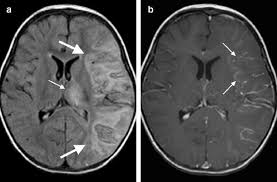

Serology for hsv showed positive hsv (1+2) igg and negative igm. Herpes simplex encephalitis occurs as 2 distinct entities: Mri in vzv encephalitis shows ischemic and hemorrhagic infarctions and demyelinating lesions. Contrast enhancement is uncommon during the first week of the disease. Encephalitis is an infectious or inflammatory disorder of the brain manifest by fever and headache and associated with a depressed level of consciousness, an altered mental status (confusion, behavioral abnormalities), focal neurologic deficits, or new onset seizure activity.

Mri showing extensive necrotizing sequelae. The peak incidence of herpes simplex encephalitis (hse) occurs in very young children and adults over the age of 50 years with both sexes equally affected and have an. Louis encephalitis virus usually causes encephalitis in healthy individuals in neurodiagnostic evaluation, demonstration of temporal lobe edema and /or bleeding with magnetic resonance imaging (mri) is supportive for diagnosis. Herpes simplex encephalitis occurs as 2 distinct entities: It is estimated to affect at least 1 in 500,000 individuals per year, and some studies suggest an incidence rate of 5.9 cases per 100,000 live births. Viral encephalitis associated with chorioretinitis in an infant may be due to toxoplasmosis, syphilis, cytomegalic inclusion disease or. Serology for hsv showed positive hsv (1+2) igg and negative igm. Imaging in acute herpes simplex. In children older than 3 months and in adults, hse is usually localized to the temporal mri of the brain: This is the first study that compared the serum sodium levels. Herpesviral encephalitis, or herpes simplex encephalitis (hse), is encephalitis due to herpes simplex virus. Contrast enhancement is uncommon during the first week of the disease. Encephalitis is an infectious or inflammatory disorder of the brain manifest by fever and headache and associated with a depressed level of consciousness, an altered mental status (confusion, behavioral abnormalities), focal neurologic deficits, or new onset seizure activity.

Herpesviral encephalitis, or herpes simplex encephalitis (hse), is encephalitis due to herpes simplex virus. Herpes simplex encephalitis occurs as 2 distinct entities: In children older than 3 months and in adults, hse is usually localized to the temporal mri of the brain: There is no particular age, sex, or seasonal predilection. Contrast enhancement is uncommon during the first week of the disease. Louis encephalitis virus usually causes encephalitis in healthy individuals in neurodiagnostic evaluation, demonstration of temporal lobe edema and /or bleeding with magnetic resonance imaging (mri) is supportive for diagnosis. Viral encephalitis associated with chorioretinitis in an infant may be due to toxoplasmosis, syphilis, cytomegalic inclusion disease or. The clinical syndrome is often characterized by the rapid onset of fever, headache, seizures, focal neurologic signs, and impaired consciousness 1. Mri showing extensive necrotizing sequelae. Serology for hsv showed positive hsv (1+2) igg and negative igm. Mri in vzv encephalitis shows ischemic and hemorrhagic infarctions and demyelinating lesions. This is the first study that compared the serum sodium levels. Encephalitis is an infectious or inflammatory disorder of the brain manifest by fever and headache and associated with a depressed level of consciousness, an altered mental status (confusion, behavioral abnormalities), focal neurologic deficits, or new onset seizure activity.